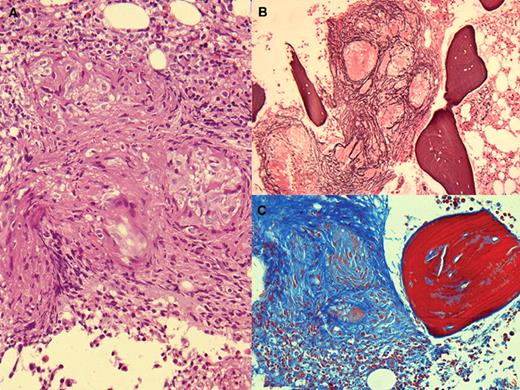

A 44-year-old woman was evaluated for a 2-month history of asthenia, weight loss, and nightly fever. She had no hepatosplenomegaly or adenopathy. The complete blood count and the basic chemistries were normal as were the radiologic examinations of the chest and abdomen. Cultures of blood and urine and serologic studies for rickettsia, chlamydia, brucella, Legionella, and Mycoplasma were negative. Sputum for Mycobacteria was negative. Bone marrow aspirate showed no abnormalities of marrow elements but noncaseating granulomata were observed in the H&E stain of the biopsy (panel A). In addition, the silver nitrate stain (panel B) and Masson trichrome (panel C) showed fibrosis. The acid-fast stain and marrow cultures were negative. Angiotensin-1 converting enzyme was shown to be elevated (119 UI/L).

A diagnosis of sarcoidosis was suggested based on the marrow, clinical findings, and the elevation of angiotensin-1 converting enzyme. Adalimumab was initiated and the patient improved with the disappearance of constitutional symptoms and fever. A follow-up bone marrow has not yet been performed.